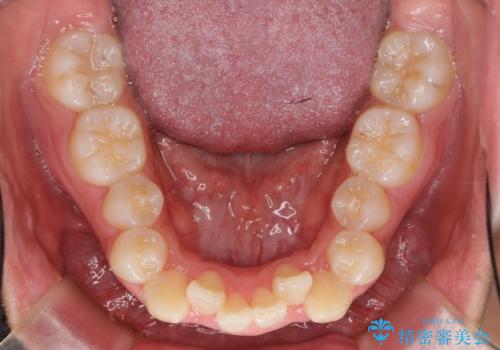

八重歯 抜かずにマウスピース矯正治療

- 八重歯を主訴に来院。

(1)口元を下げるなら、上下左右抜歯でワイヤー矯正

(2)奥歯を後ろに下げ、歯並びを拡大し、歯を少し削って抜かずにインビザライン矯正 矯正用ミニスクリュー併用 口元は下がらない

の選択肢から選んでもらいました。

目立たない装置希望とのことで、(2)を選択されました。

抜歯をしていないので口元は変わっていません。

八重歯も重症でなければインビザラインでも並びを歯を抜かずに整えることができます。